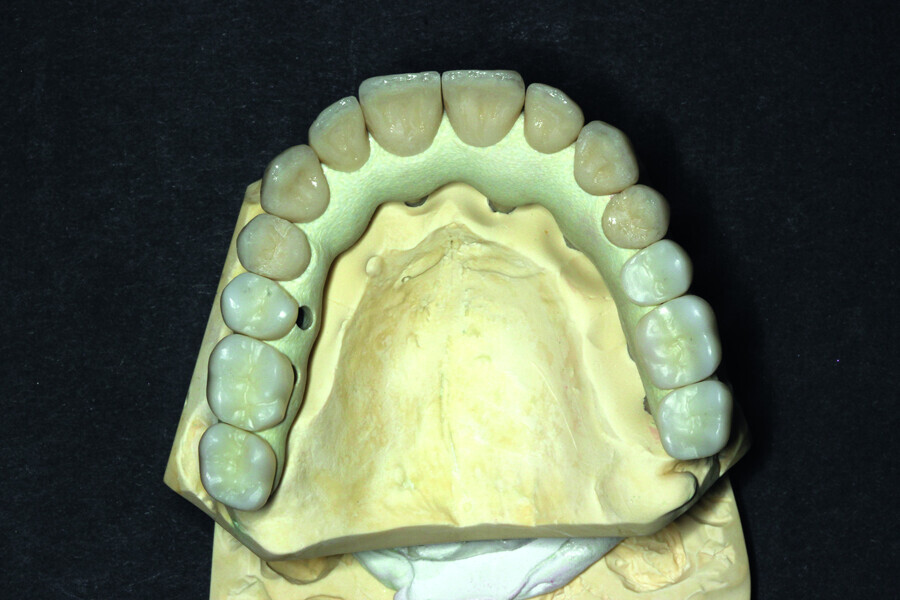

Fig. 13: Porcelain crowns prepared for testing.

Fig. 14: Porcelain crowns based on a model prior to veneering by means of a pink composite.